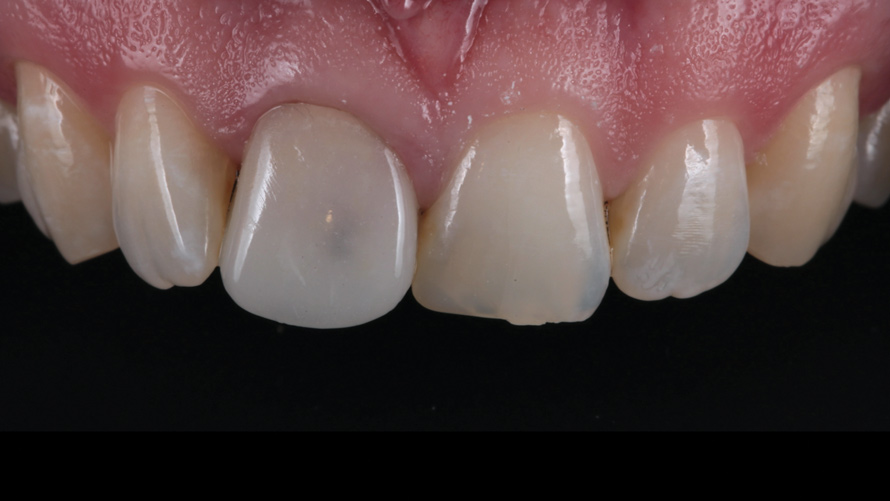

(2.) Case 2: Patient presentation of an asymptomatic, unesthetic full-coverage ceramic restoration on the maxillary left central incisor.

Figure 2

Two patients presented separately to the clinic for the elective replacement of an asymptomatic, discolored, full-coverage restoration on a single maxillary central incisor. The chief complaints of each patient were based solely on esthetics (Figure 1 and Figure 2). During the intraoral examination of each tooth, both patients demonstrated an unremarkable occlusion, good oral hygiene, firm gingiva, probing depths of 2 mm to 3 mm, no bleeding within the sulcus, and tooth mobility that was within normal limits. The results of all sensitivity tests, which included cold, percussion, and palpation, were negative.